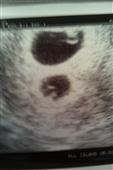

Well the appt was amazing! IT's TWINS!!!!!!!!!!!!!!

We saw 2 little heartbeats and they are both measuring right on track!

We are so excited and in shock!

here are my little lentils: